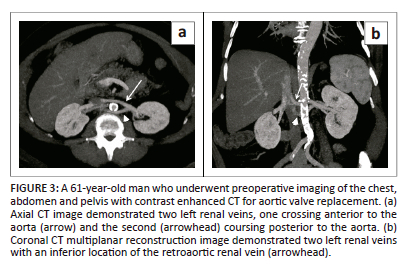

Circumaortic left renal vein

Two left renal veins are present on the left side with one coursing anterior to the aorta and other posterior to the aorta. It results from persistence of the posteriorly located inter-supracardinal vein anastomoses as well as the anteriorly located inter-subcardinal vein anastomoses that form a venous ring around the aorta (Figure 3). The reported prevalence ranges from 2.4% to 8.7%.1 The posterior renal vein is 1 cm - 2 cm inferior to the normal anterior vein. The left adrenal vein drains into the superior renal vein. The left gonadal vein drains into the inferior renal vein. Knowledge of this variation is significant in preoperative planning prior to nephrectomy and catheterisation for renal venous sampling. It can also mimic retroperitoneal adenopathy.7,9 It is also important to recognise this variation prior to positioning of the IVC filter.18 These patients may uncommonly present with hypertension, haematuria and varicoceles.19